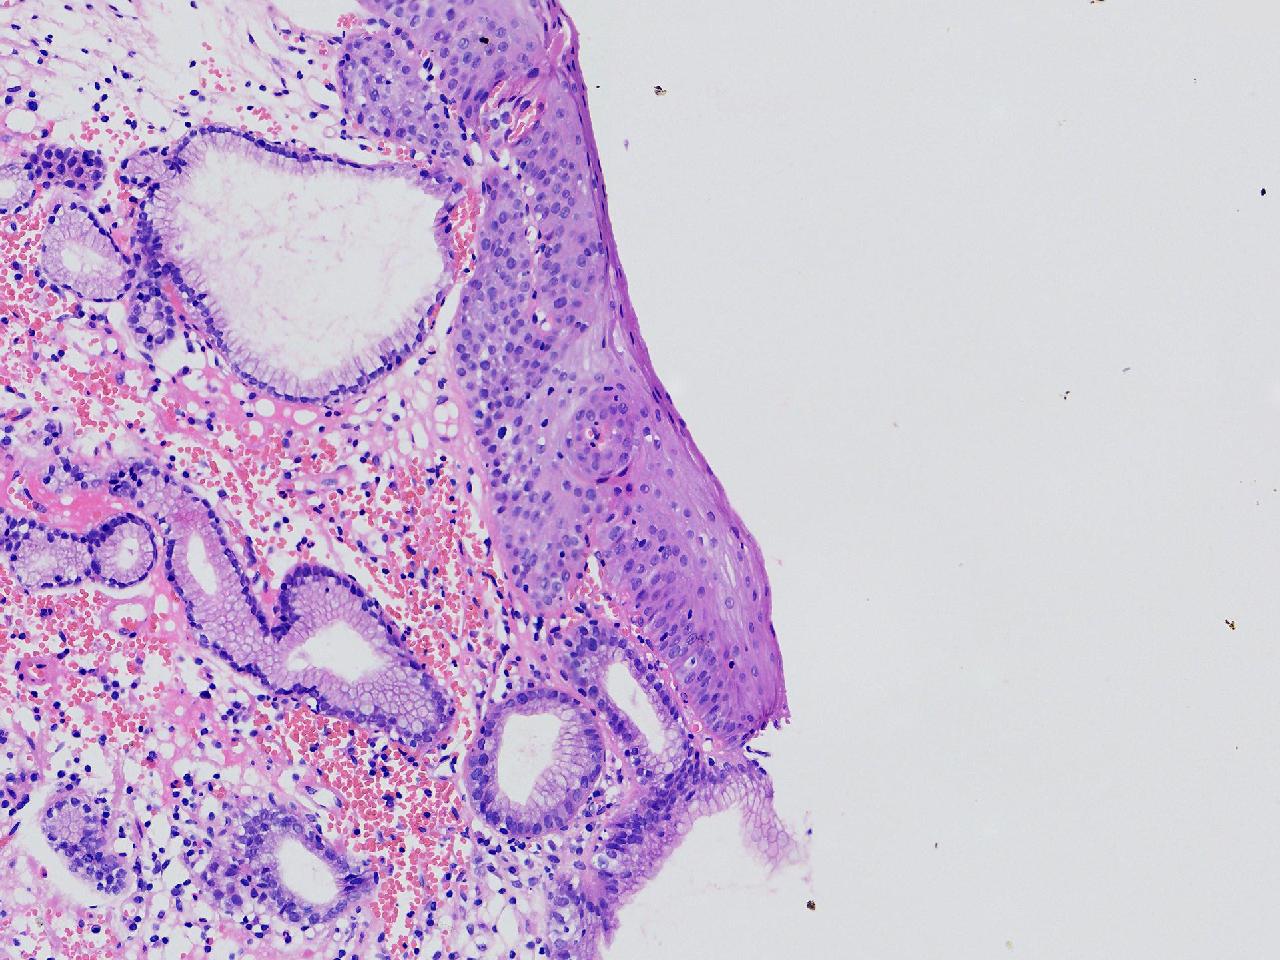

女,38岁,食管距门齿38cm处见一扁平隆起,表面粗糙,活检1块,质软,弹性可。

食管活检

灰白色不整形软组织1块,直径0.2厘米。

结合取材部位排除Barrett食管

粘膜慢性炎。

Barrett食管,粘膜慢性炎。